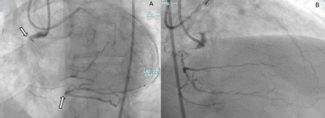

Coronary artery management. Because the circumflex coronary artery also lies within the atrioventricular groove, it can have a close proximity to the CS. There is a risk of coronary artery compromise, which can be managed to avoid anything other than temporary compression. Coronary angiography was performed immediately after pulling tension on the device. Also, after deployment of the proximal anchor, but before decoupling, a coronary angiography was performed. This temporary compression was observed in 7/17 patients (41.2%) (Figure 5). This was addressed by a stepwise approach. First, if there was only a partial compression (not an occlusion) of the circumflex artery, intracoronary instillation of nitroglycerin was attempted to relax the spastic artery. This was successful in 1/17 cases (5.9%). If this was unsuccessful, reduction of the tension on the system was attempted (prior to placing the proximal anchor), with assessment of MR reduction after this lesser degree of tensioning. If this was acceptable, and the coronary compromise was minimal or absent, the proximal anchor was then deployed in this location. This was successful in 1/17 cases (5.9%). The next option was to recapture the device and change to a shorter device, to allow placement of the distal anchor more proximally, to avoid compressing the artery. This was successful in 2/17 cases (11.8%). Finally, if the device under tension led to a significant reduction in MR, but coronary compression could not be solved by previous maneuvers, a coronary stent was placed in the coronary artery to protect the artery against the external compression from the device. Stenting was successfully performed in 2/17 cases (11.8%). Only 1/17 patients (5.9%) could not be implanted due to coronary artery compression of a large marginal coronary artery branch, providing an implant success rate of 94.1%. Of interest, in 1/7 cases of coronary artery compression, the compression was in the right coronary artery, which was treated with a stent. This patient underwent a coronary angiography 5 months after initial procedure and no restenosis could be observed. The other patient with need for coronary stenting of the circumflex artery was followed up non-invasively (echocardiography and treadmill exercise test), which showed normal findings.